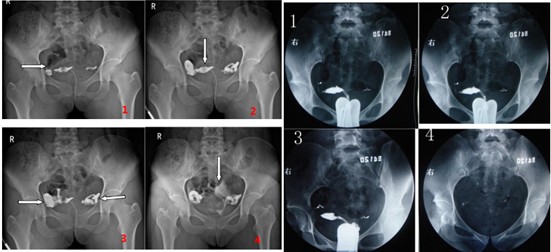

所谓的输卵管水肿,是输卵管内积聚了体液,导致输卵管内壁纤毛无法自由摆动抓卵,甚至可能因而阻塞。一般检查的方式包括了输卵管通液B超、输卵管子宫 造影X 光摄影或是腹腔镜手术。产生的原因大多是先前曾经骨盆腔感染导致发炎,或是罹患严重子宫内膜异位症。